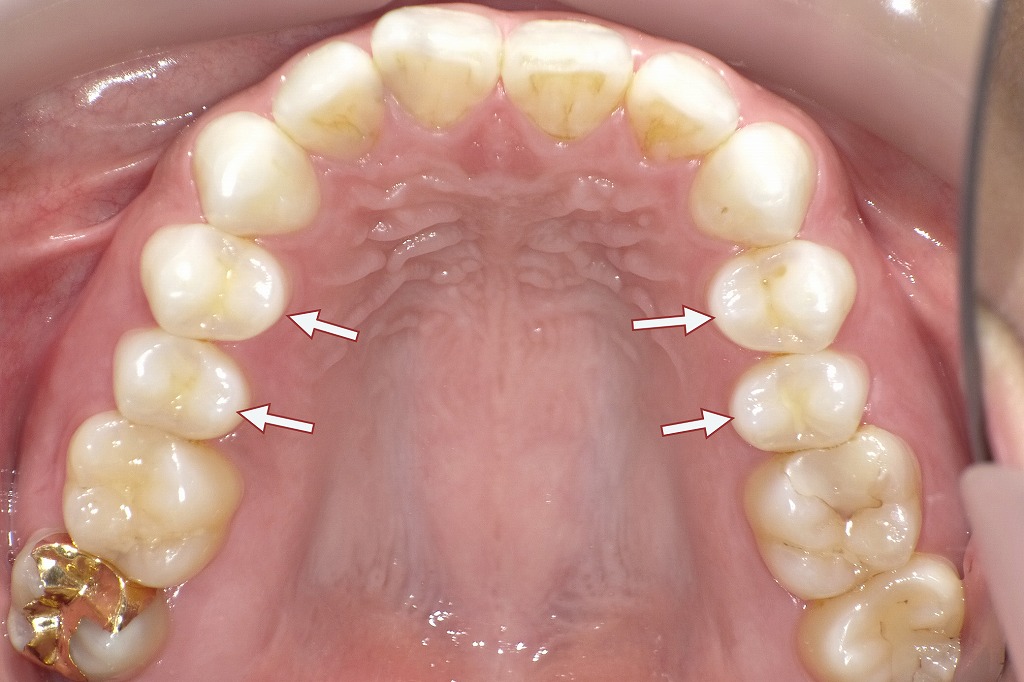

下記の口腔内写真は歯の萌出スペースが足りない、あるいは周囲の歯との位置関係が乱れている場合、小臼歯が本来の歯列から外れて生えてしまうことがあります。これが「頬側転移(きょうそくてんい)」や「舌側転移(ぜっそくてんい)」と呼ばれる現象です。